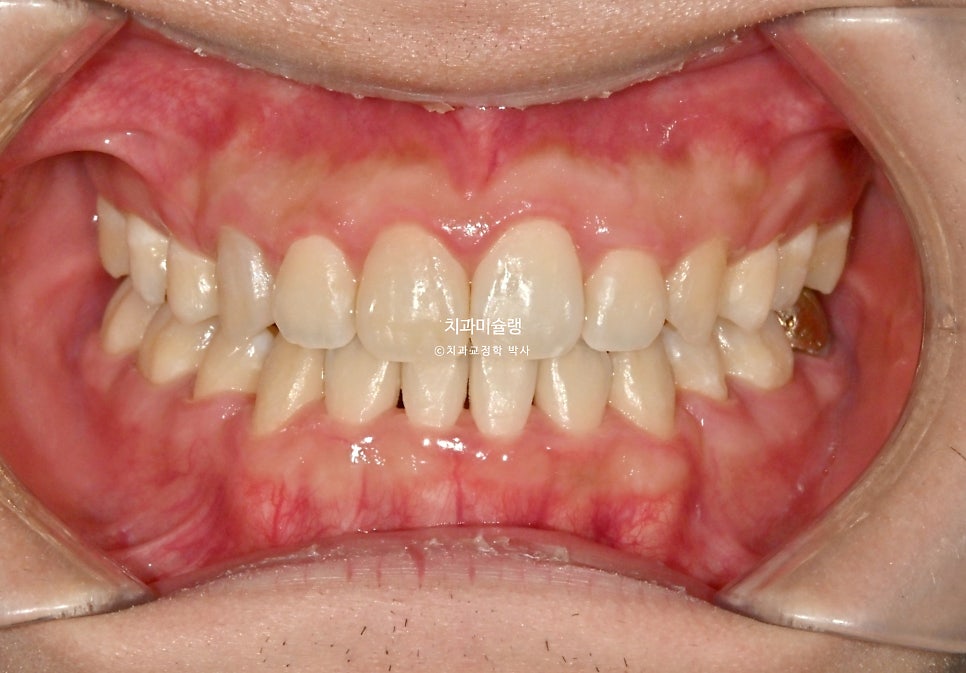

2026년 2월 치료 완료

중심선은 정확히 맞으며 앞니 교합은 좋습니다.

어금니 교합은 물샐틈 없는 1급 교합관계를 보입니다.

치료 결과 비교

이제 전후 비교 볼게요.

총 치료기간은 2년이 채 안걸린 1년 11개월 이며 총 내원 횟수는 10회 입니다.